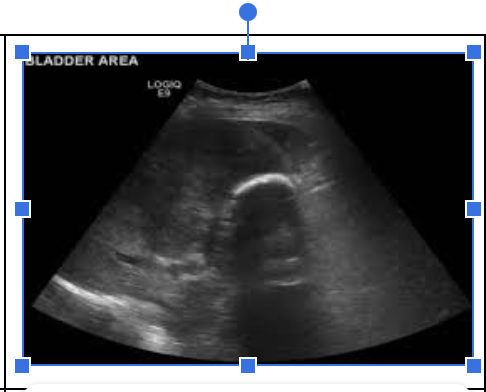

What pathology is in the image below?

Porcelain Gallbladder - right echogenic, posterior shadow